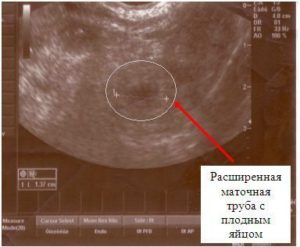

При закреплении зиготы вне матки, определить это на УЗИ достаточно сложно. Даже самый чувствительный аппарат не способен идентифицировать зиготу в маточных трубах или других органах репродуктивной системы.

Подозрения на внематочную беременность возникает при одновременном выполнении следующих условий:

• положительный тест, растущий уровень ХГЧ;

• отсутствие эмбриона в матке;

• дискомфорт в брюшной полости.

Через 4-5 недель после зачатия врач может обнаружить увеличение органа, в котором прикрепился эмбрион. В первые 2-3 недели после оплодотворения яйцеклетки увидеть на УЗИ замершую беременность невозможно.

Закрепиться оплодотворенная яйцеклетка может в любом месте: маточная труба, яичник или прямо на тканях брюшины.

Это серьезная патология, которая требует оперативного вмешательства и может угрожать жизни женщины.

Другой уже опасной ситуацией, из-за какой зародыш может быть не видно, является внематочная беременность. Плодное яйцо может локализоваться в трубах, полости живота. И если его размеры малы, врач не сможет увидеть его с помощью ультразвука.